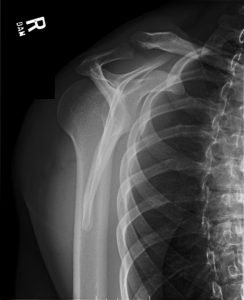

Posterior Shoulder Dislocation, Y View XR. JETem 2017